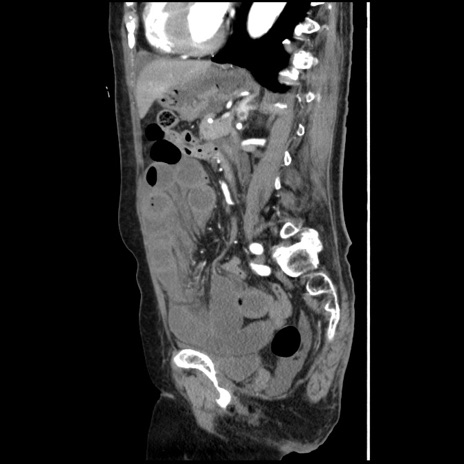

冠状断像

【症例】80歳代女性

【主訴】腹痛

【現病歴】8時間前から腹痛あり来院。

【既往歴】糖尿病、脂質異常症、子宮体癌にて子宮全摘術

【身体所見】意識清明・会話良好だが腹痛で苦悶様、全腹部にわたって反跳痛と圧痛あり

【データ】WBC 13600、CRP 0.14、LDH 224、CK 90